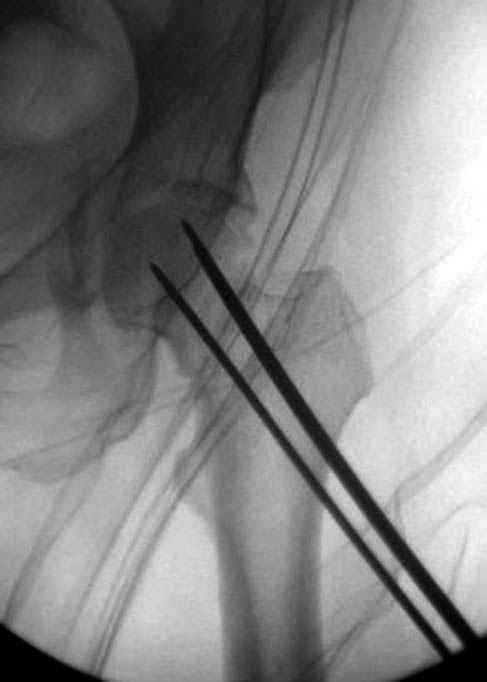

Уважаемые коллеги! С прошедшеми Вас праздниками. Теперь ближе к трудовым будням. Поступила 16 летняя девушка неделю назад. Механизм травмы падение с 5 этажа. Краткий диагноз:закрытый перелом левой ключицы, левого плеча, закрытый вертикально и ротационно нестабильный перелом костей таза:закрытый перелом левой подвздошной кости, переломы лонной кости справа, перелом обоих колонн вертлужной впадины слева;субкапитальный перелом шейки левой бедренной кости со смещением. По тактике лечения таза возникли следующие вопросы: 1. С чего начать - фиксации переломов вертлужной впадины или устранения деформаций таза? 2. Надо ли фиксировать шейку или фиксировать бедро в аппарате вместе с тазом, а после сращения таза планировать ТЭП ТБС? Если имеются еще какие подводные камни, будем рады выслушать.Спасибо.

Долгое ожидание повышает риск АВН головки,

рекомендуется ургентная фиксация шейки в первые сутки, а в дальнейшем таз.

В данный момент скелетное вытяжение поучается через перелом шейки, а фиксированный перелом шейки будет участвовать в процессе вытяжения через каннюлированные шурупы.

Перелом шейки смогли зафиксировать через пару дней, ацетабулум до сих пор не оперирован, на вытяжении.

Из-за упущенного времени (три недели с момента

поступления) ацетабулум ведем консервативно.

На снимке ацетабулума редко встречающийся очень низкий перелом, наверное, трудно было репозицию через один доступ? Перелом как бы замкнулся в квадрилатеральной поврехности.

Фиксацию шейки провели когда получили окно, быстро

перкутанно смогли провести шурупы.